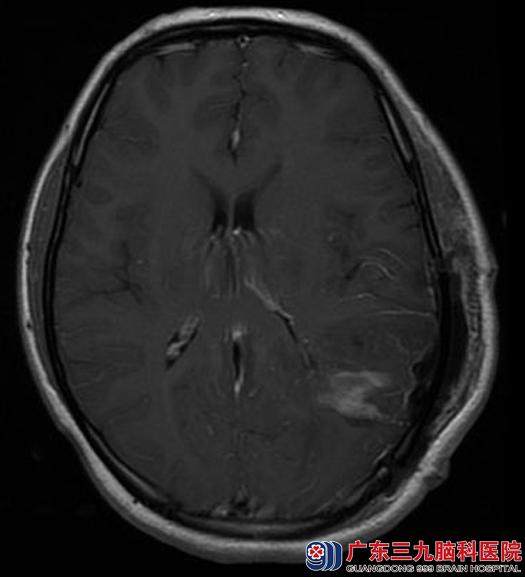

一过性的眼睛发黑竟然是脑肿瘤造成的,小芳和她的家人似信非信地来到广东三九脑科医院,综合神经外科的鲁明主任也考虑脑肿瘤的可能性大,进一步行头颅MR检查,结果提示:左侧侧脑室三角区为主,示一不规则病变,大小约37.3mm×63.7mm×43.0mm。

全麻下行左侧三角区脑膜瘤切除术,术中显微镜下见肿瘤边界清楚,质韧,前至颞叶,后至枕叶,与左侧脑室后角粘连,镜下全切除肿瘤,术后病理证实:过渡型脑膜瘤。